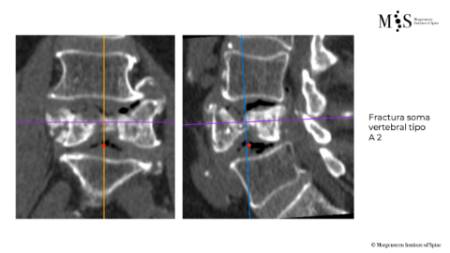

Clinical case example of a lumbar vertebral body resection (corpectomy) and reconstruction of a burst fracture at level L4.

Vertebral body resection (corpectomy) and reconstruction of complex vertebral and burst fractures

Severe vertebral body fractures, i.e. conminute and burst fractures, may require a partial vertebral body resection (corpectomy) and reconstruction with an expandable vertebral body cage. Especially severe fracture cases are also those with a bone fragment moving into the spinal canal that compresses on neural structures, such as the spinal cord and causes spinal canal stenosis. Corpectomy allows to resect most of the fractured body, including the bone fragments pushing on the nerves and intruding into the spinal canal. The vertebral body reconstruction is usually rounded up with a posterior augmented instrumented fusion of the adjacent levels to the fracture. All of this allows a proper healing of the fracture and the patient to recover without pain.